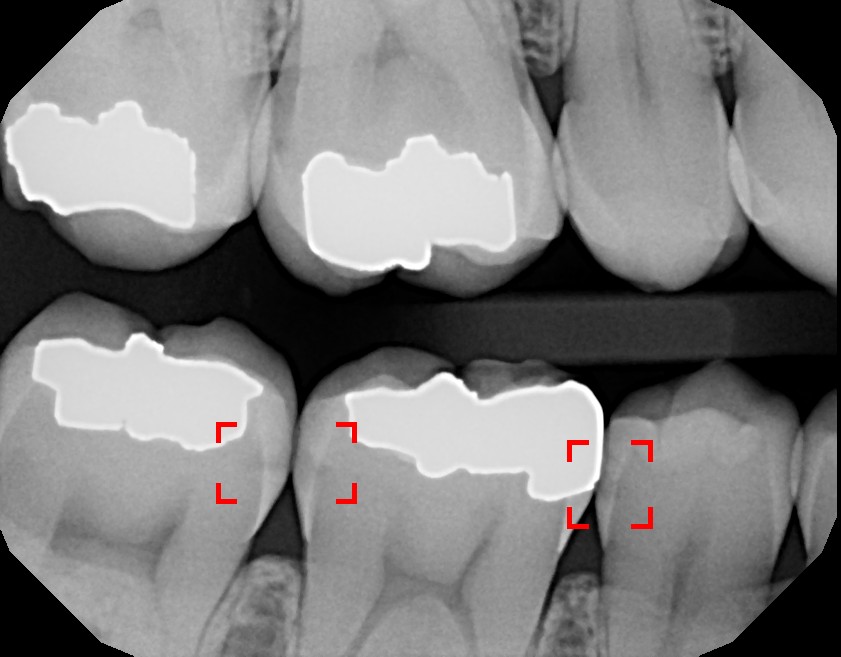

Xray Image of Teeth with Fillings Stock Image Image of gums X Ray Of Tooth With Filling Here is a picture of what a different tooth with decay underneath of an existing filling looks like. They are able to diagnose issues like cavities early and fix them quickly, helping patients avoid unnecessary pain, cost, and further damage. The images produced can show the dentist or hygienist details that cannot be seen with the naked eye, such as. X Ray Of Tooth With Filling.

XRay Example of an Amalgam Filling and Tooth Decay The Center For X Ray Of Tooth With Filling Here is a picture of what a different tooth with decay underneath of an existing filling looks like. Dental cavities are one of the most common worldwide dental problems, affecting millions yearly. For example, under a filling, or between the teeth. There is no real explanation for it usually. They are able to diagnose issues like cavities early and fix. X Ray Of Tooth With Filling.